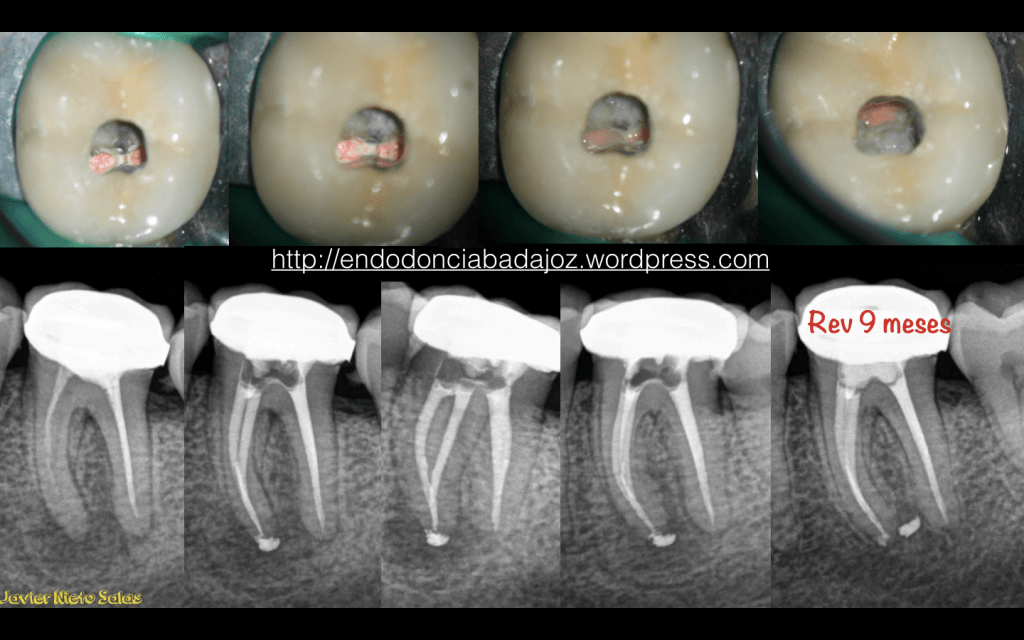

Como veremos en estos dos casos que subimos hoy, si realizamos un tratamiento correcto, que nadie dice que sea sencillo, obtendremos , en la generalidad de los casos, un MUY BUEN PRONÓSTICO.

2) Caso B: Conductos omitidos y subobturación del conducto distal. Vemos la regeneración de la lesión a los 9 meses.